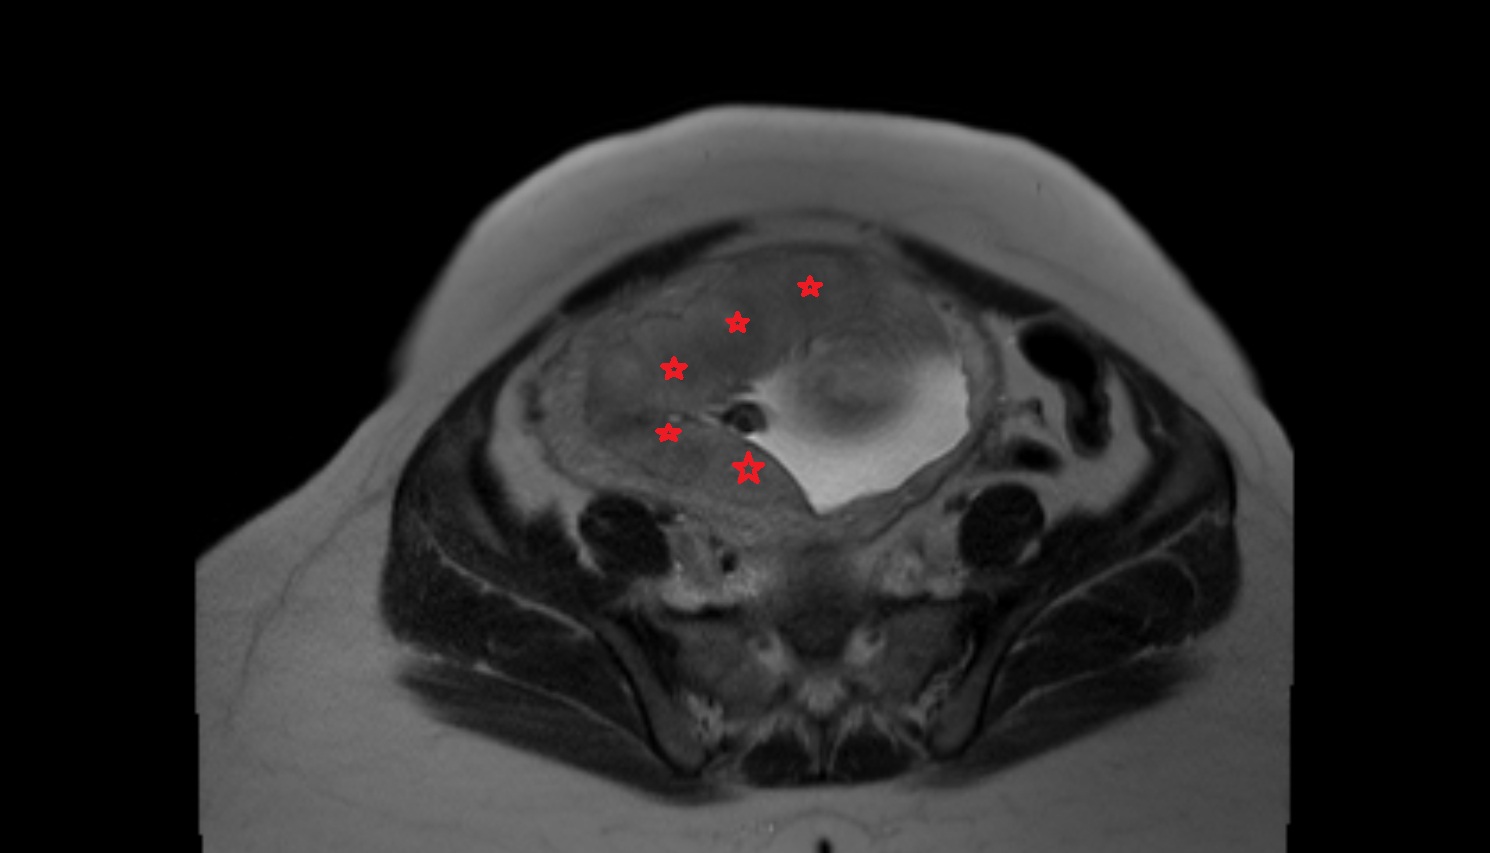

- Placenta

- Uterus (pregnancy)

- Amniotic fluid

- Umbilical cord

- Urinary Bladder in Pregnancy

- Cervix in Pregnancy

- Fetal brain

- Fetal caudate nucleus

- Fetal thalamus

- Fetal cerebellum

- Fetal lateral ventricle